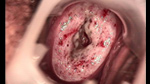

• 宮頸息肉 leep術(shù)一周后宮頸息肉 leep術(shù)一周后

• 宮頸息肉 leep術(shù)兩周后宮頸息肉 leep術(shù)兩周后

• 宮頸息肉 leep術(shù)三周后宮頸息肉 leep術(shù)三周后

• 宮頸息肉 leep術(shù)50天后宮頸息肉 leep術(shù)50天后